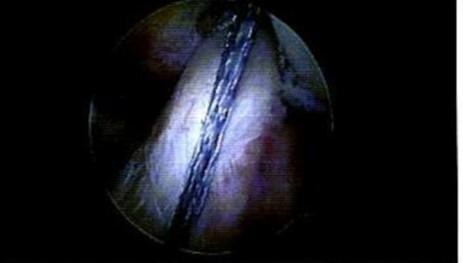

SURGICAL TECHNIQUE AND NON-OPERATIVE MANAGEMENT

All surgeries were performed in an open manner during which each end of the tendon was debrided of abnormal tissue and repaired in a side to side fashion with No. 2 Fiberwire sutures (Arthrex, Naples Fl). A backslab (below knee half cast) was placed on the ankle in plantarflexion and converted to a boot with elevated heel wedges at the twoweek mark. The management of those who were treated non-operatively differed based on clinician. However, these patients were all managed by some variation of initial nonweight bearing in plantar flexion alongside progressively reduced heel lifts and gradual restoration of weight-bearing, with referral for physical therapy